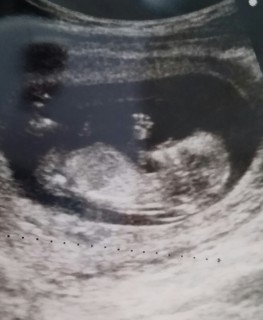

12w。3回目の診察!!!51.2mm。 4DエコーをDVDに録画してくれる病院なので4Dエコー見ながら、DVDお願いできますか?て聞いたら「それ診察の前に言って欲しかったねー」て冷たい感じで言われました。そんな事情、初マタの私は知らんし!もともと短気な私は病院変えようかなてガチで思ったしw写真もぶれてるしwまーいいやw「うん!順調だね♪」なんて言われたら何でも許せる。今の私。。。笑

12週目突入(^-^)v4Dも一緒に載せてみました(*^^*)男の子???ってちょっと思ったけど来月までのお楽しみ(^-^)

初めてこの日赤ちゃんが足をバタバタさせていたり、くねくね動いているのを見られて感動!思わず、あ!動いてる!!と言ってしまいました。赤ちゃんらしい形になってきてますます可愛いです。早く会いたいな。大きさは57.1mmで週数にしては少し大きめかな。

ふたり目です♪つわりが酷くて辛いけど元気にクルックル動いててママは救われました!可愛すぎるっ。CRL58mmで年齢が気になるのでNTもみてもらいNT0.6mmで全く問題ないとのことでした。大股びらきでよく見ると中央に何やらおちんちんらしきものが…。上が女の子なのでとても楽しみです♪